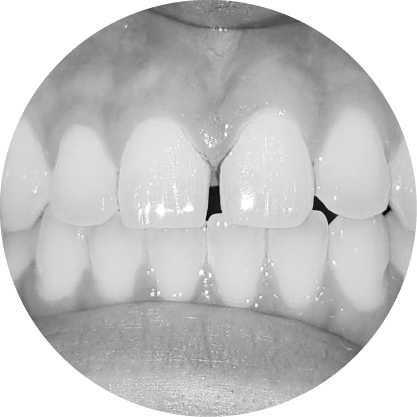

ช่องว่างระหว่างฟัน (Diastema)

การปิดช่องว่างระหว่างฟัน เพื่อรอยยิ้มที่สมบูรณ์แบบ

"ช่องว่างระหว่างฟันหรือไดแอสเทมา หมายถึงช่องว่างระหว่างฟันที่เห็นได้ชัด ซึ่งอาจเป็นปัญหาทางความงามสำหรับหลายๆ คนการจัดฟันสามารถปิดช่องว่าง เหล่านี้ได้อย่างมีประสิทธิภาพทำให้มีรอยยิ้มที่สม่ำเสมอและสวยงาม"

ตัวอย่างในชีวิตจริง